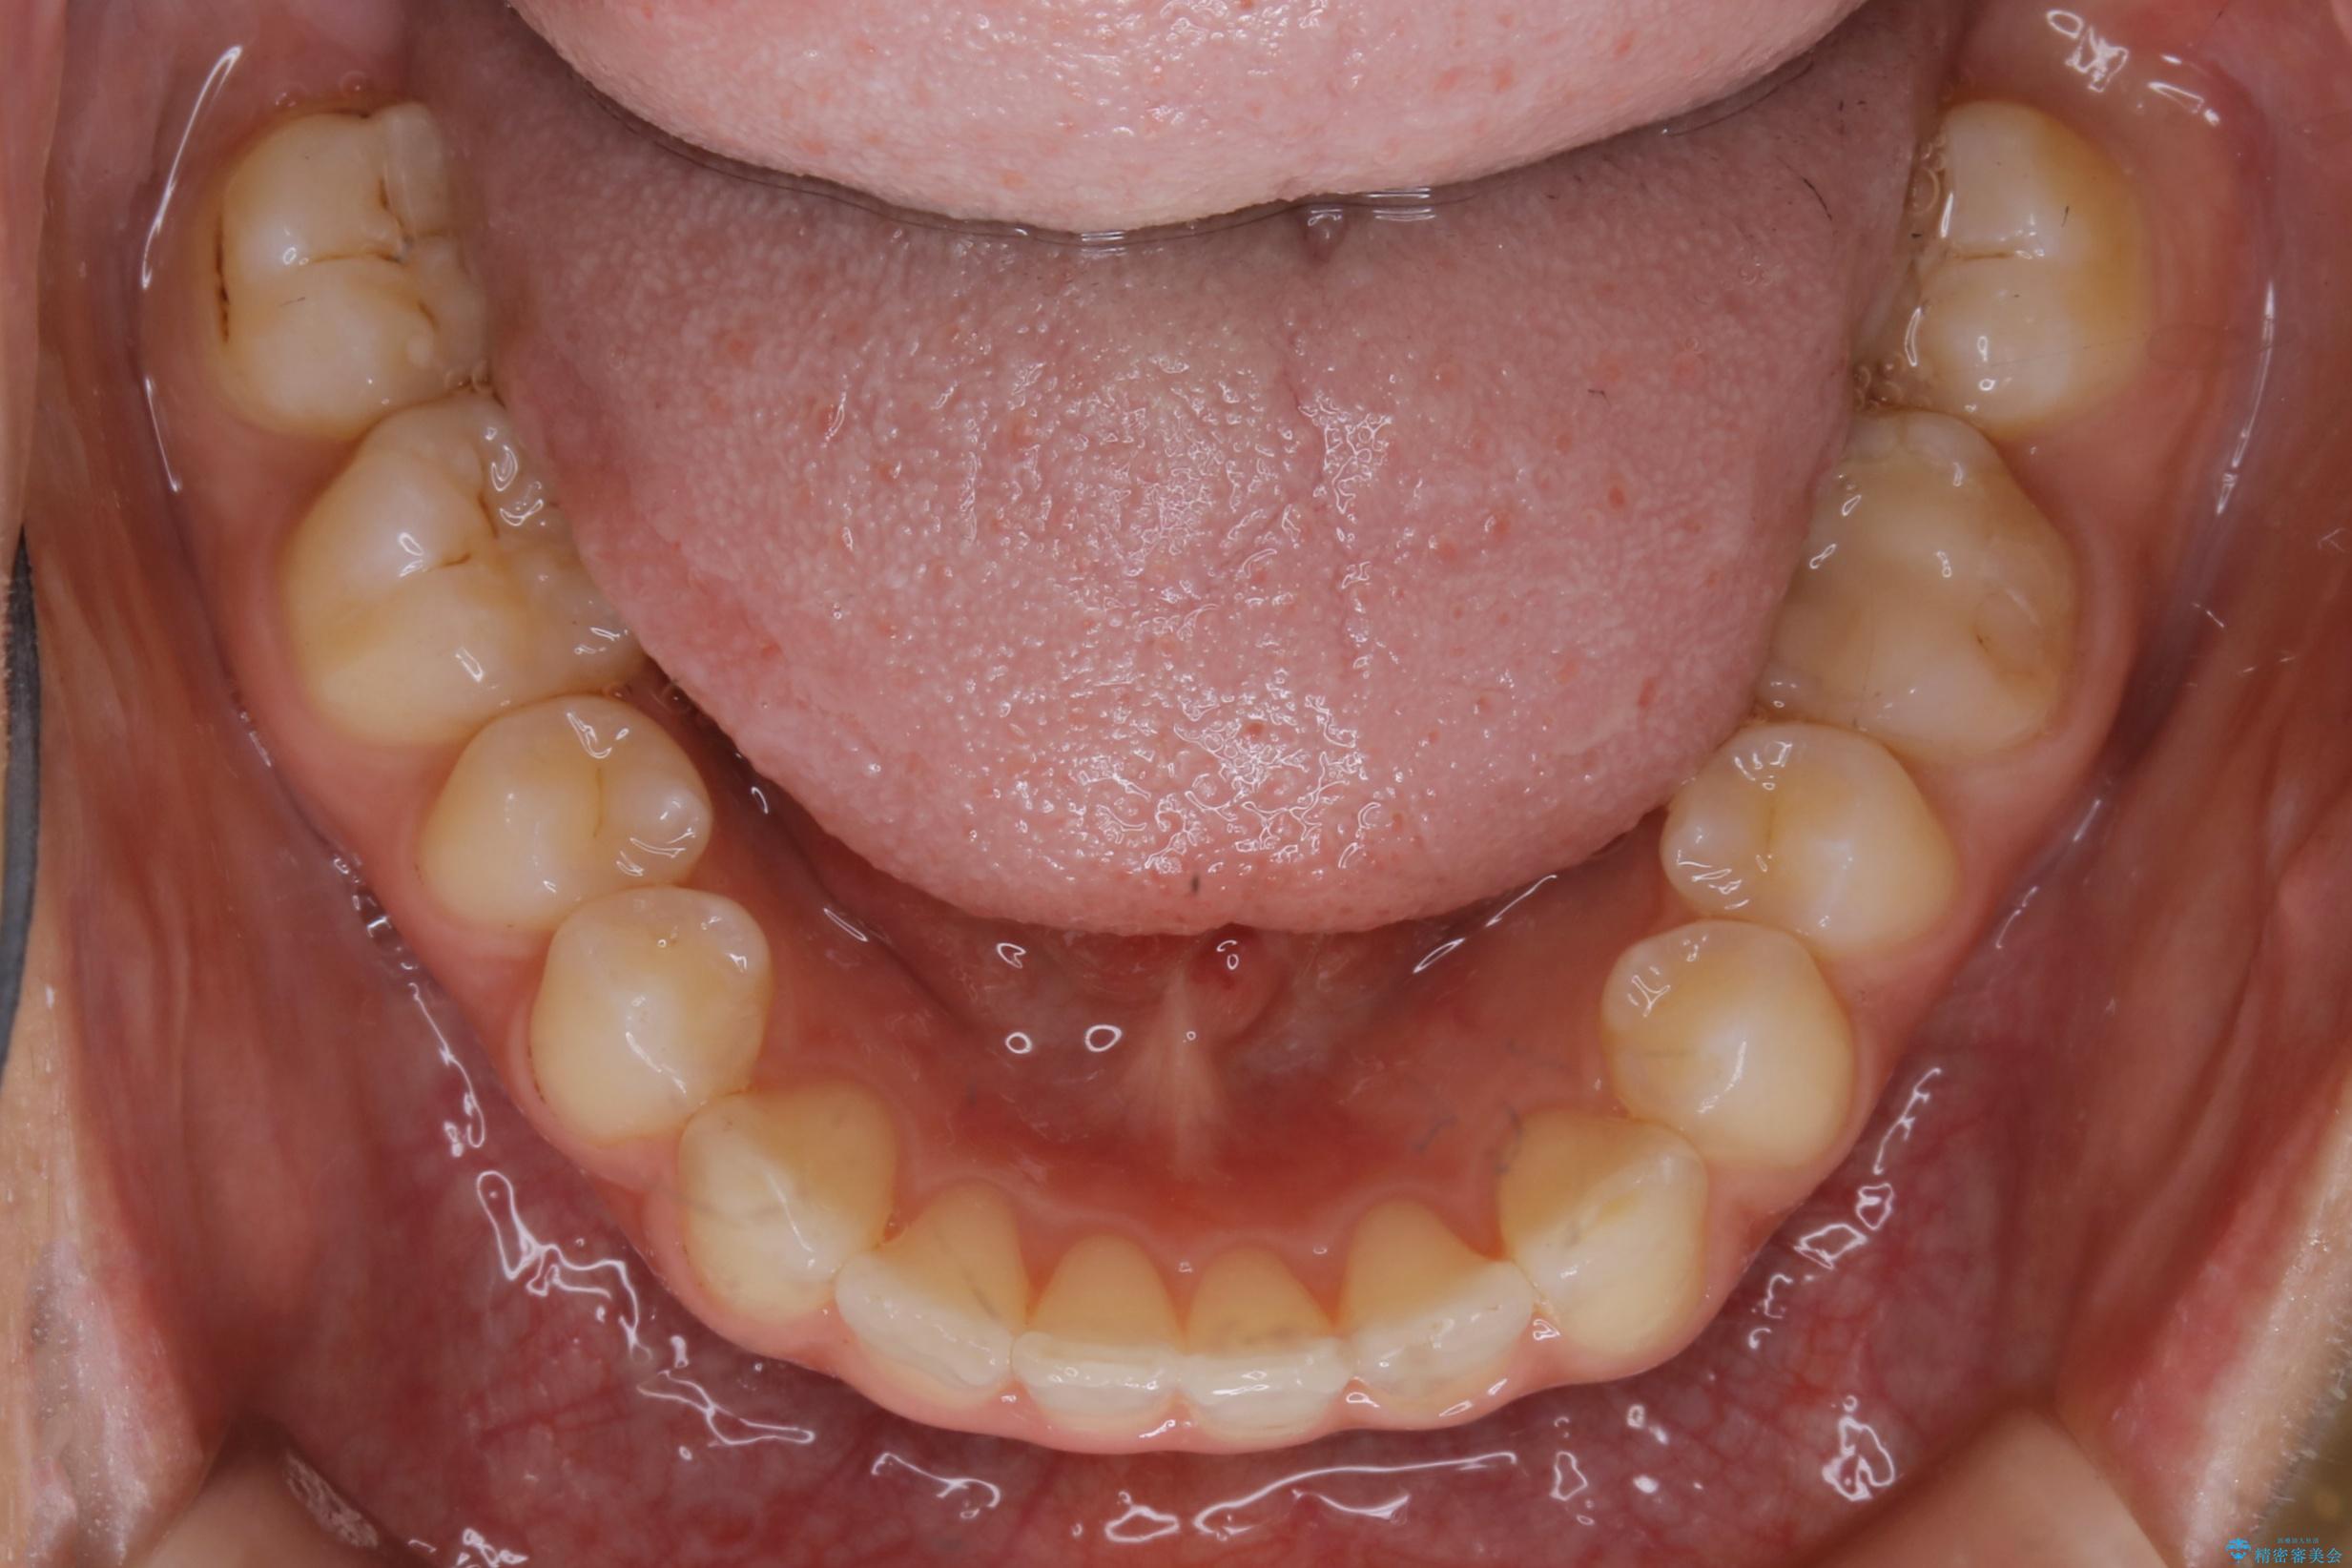

歯並びが悪くなる原因の一つに「歯列弓の狭窄」というものがあります。

奥歯や前歯が内側(舌側)に倒れ込んでしまったり、歯が生えてくる位置が内側になってしまうことにより歯並びのアーチが狭くなってしまうことを言います。

このような場合、歯並びのアーチを拡大してあげるだけでもガタつきを無くすためのスペースがかなり作れることがあります。